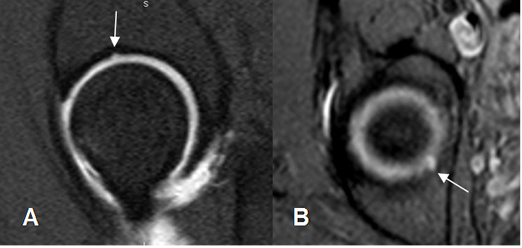

Fig 115. Quiste paralabral.

A: Rx AP. Prominencia del borde lateral de la cebaza femoral, por pinzamiento tipo cam.

B: RM coronal en T2 y C: RM coronal en STIR. Imagen quística e hiperintensa en ambas secuencias, hacia la región superoexterna del reborde acetabular, que corresponde a quiste paralabral.